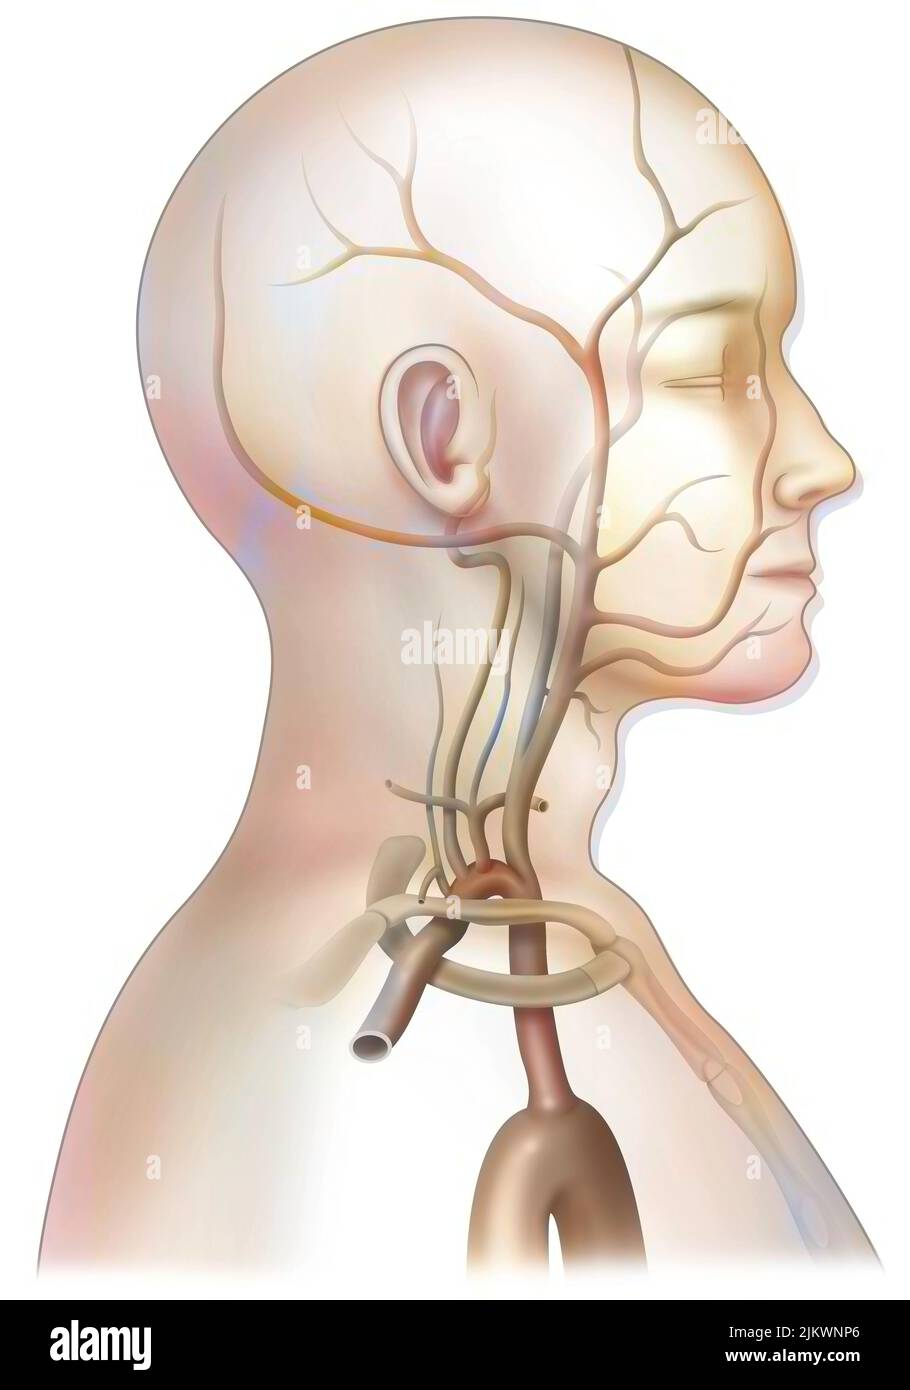

RFR3P9KC–Illustration der Blutversorgung des Gehirns. Das Gehirn hat wenig Kapazität, Nährstoffe zu speichern, und benötigt eine hohe Versorgung mit Sauerstoff und Glukose.

RF2SGJF64–Anatomisches Diagramm der zerebralen Durchblutung. Sie ist für die Aufrechterhaltung der Gehirnfunktionen und für die Versorgung mit Sauerstoff und Nährstoffen von entscheidender Bedeutung.

RF2SGJF65–Anatomische Darstellung der zerebralen Durchblutung. Das Blut gelangt durch die Arterien der Karotis und der Wirbelsäule in das Gehirn und liefert Sauerstoff und Nährstoffe.